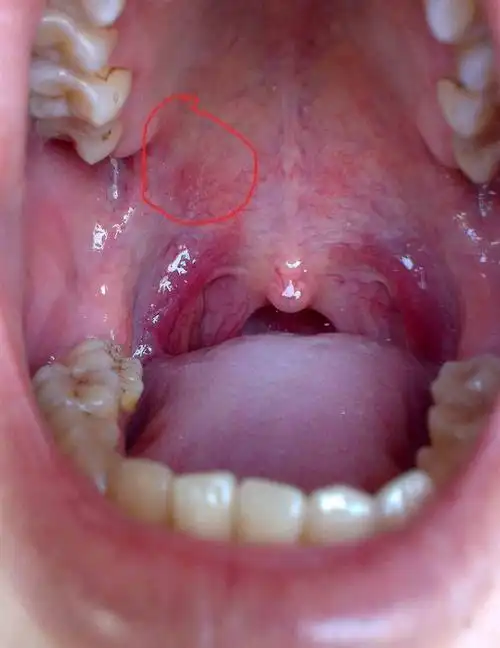

口腔上颚貌似上火发炎,感觉不像一般溃疡